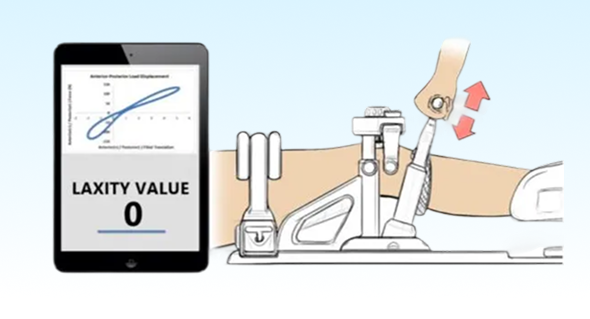

The relationship of ACL volume and T2 relaxation times to anterior knee laxity

Orthopaedic Journal of Sports Medicine.

A clinical knee arthrometer is commonly used to assess the integrity of the ACL for diagnostic and screening purposes. However, the structural properties that contribute to anterior knee laxity are not well understood. The results of this MRI-based study indicate that anterior knee laxity was largely predicted by the size of the ACL size and to a lesser extent ACL tissue quality, suggesting that those who have greater anterior knee laxity have smaller and structurally weaker ligaments. These findings support the use of cost-effective and clinically accessible measures of knee laxity to gain clinical insights into the structural quality of the ACL and potential injury risk.